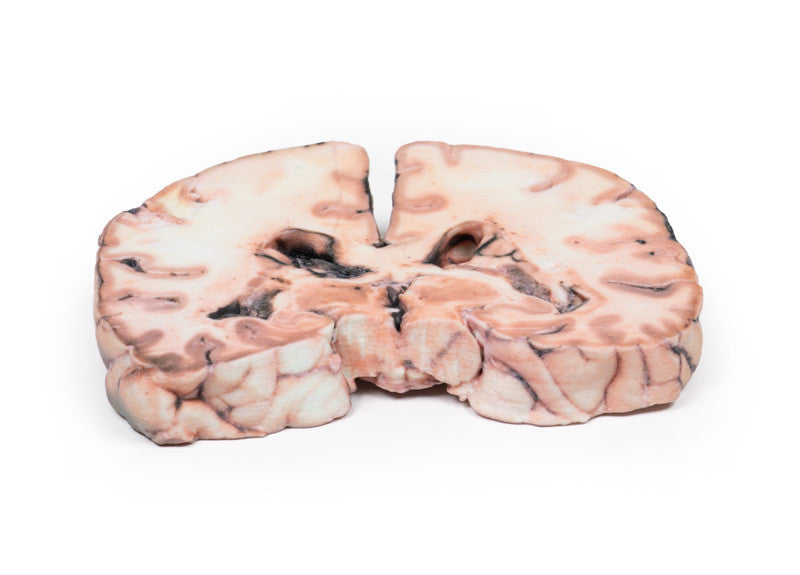

The specimen shows a large intracerebral lesion, which has obliterated the lateral ventricles and the inner 2/3 of the internal capsule and basal ganglia on the right side. It is infiltrating across the corpus callosum and distorting the aqueduct. The tumour is fairly well demarcated and vascular with numerous areas of haemorrhage and necrosis, causing its mottled variegated appearance.